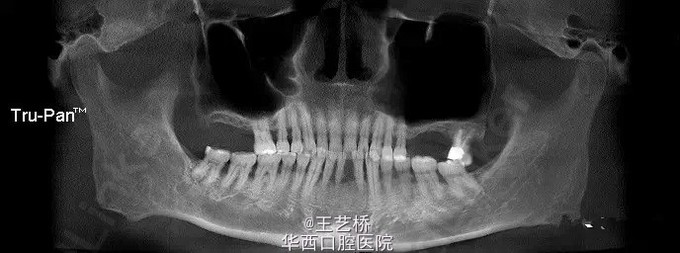

各式各样形态的上颌窦(一)

在进行上颌后牙区种植手术时,上颌窦形态是我们需要考虑吧的重要因素之一。今天收集了众多上颌窦的影像片,供大家交流学习。